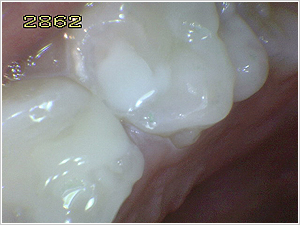

※下の3枚は差し上げた写真の例です。 |

さらに虫歯を削った後に、レジン樹脂の詰め物で修復しました。 |